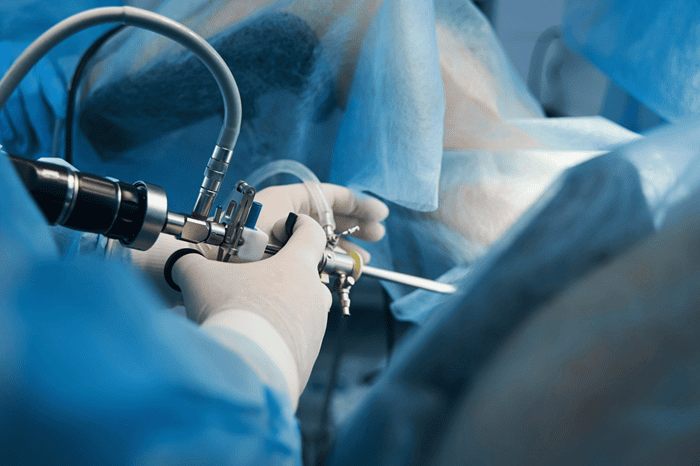

جراحی لیزری دیسک کمر (PLDD) با هدف درمان فتق دیسکها به عنوان یک روش عمل بسته معرفی شده است که با استفاده از گرما، فشار داخلی دیسک را کاهش میدهد. در این روش کمتهاجمی، پس از بیحسی موضعی و بدون نیاز به بیهوشی عمومی، سوزن باریکی با هدایت رادیوگرافی وارد دیسک فتقیافته میشود.

سپس فیبر نوری حامل اشعه لیزر، بخش کوچکی از هسته ژلهای دیسک را تبخیر میکند. این تبخیر آب دیسک که میتواند حدود ۵۷ درصد از فشار دیسک را کاهش دهد، یک خلأ نسبی ایجاد کرده و باعث میشود مواد بیرونزده دیسک به سمت داخل کشیده شوند.